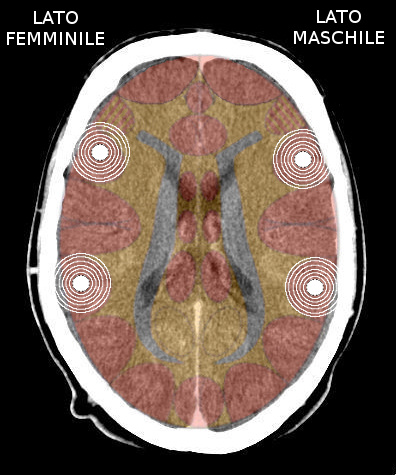

- Maschio destrimane fertile = emisfero dominante destro (è maschile);

- Maschio mancino fertile = emisfero dominante sinistro (più femminile, ma non effeminato);

- Femmina destrimane fertile = emisfero dominante sinistro (è femminile);

- Femmina mancina fertile = emisfero dominante destro (più maschile).

L'avvio di una attivazione territoriale, deprime l'ormonalità dell'emisfero colpito.

- Attivazione → lobo temporale destro = calo del testosterone (maschile); diminuisce il percepito maschile, la persona si deprime (perde aggressività);

- Attivazione → lobo temporale sinistro = calo dell'estrogeno (femminile); diminuisce il percepito femminile, la persona diventa maniacale (acquista aggressività).

Quando si attiva la corteccia insulare dominante della persona, questa si chiude ad altri SBS territoriali. Se avviene una nuova attivazione territoriale, senza che la prima si sia risolta, verrà coinvolta la corteccia insulare controlaterale e la persona entra in Costellazione.